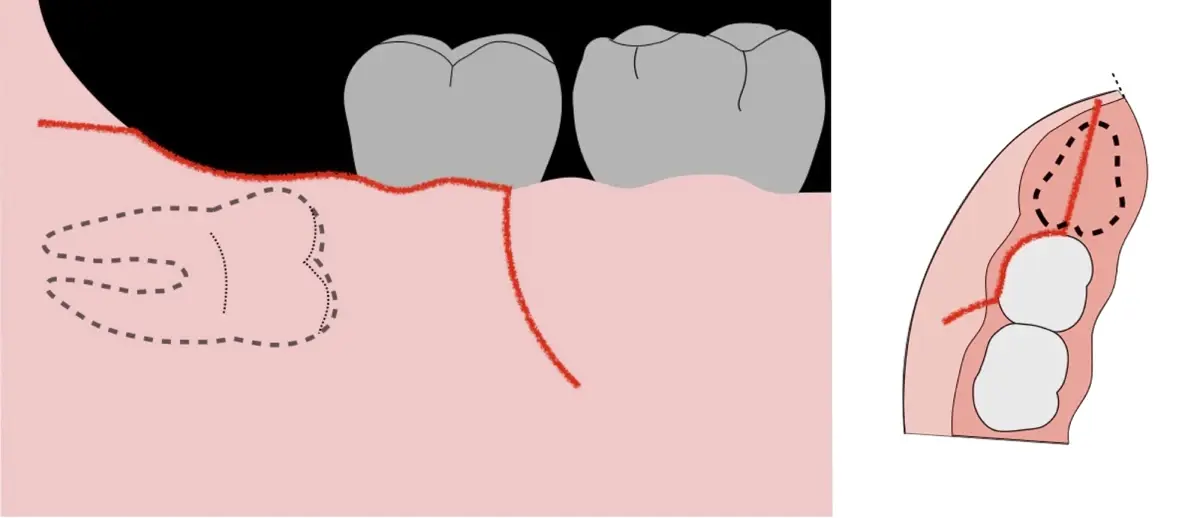

El procedimiento se inicia colocando anestesia troncular para bloqueo del nervio dentario inferior y sus ramas. Luego, se establecerá el diseño de acceso según la disposición de la molar a extraer. Para fines didácticos, se explicará cómo se realizaría la extracción de la molar de la Figura 1: se realiza una incisión horizontal a nivel de la zona retromolar hasta llegar a distal de la segunda molar, continuándose con una incisión intrasurcular hasta mesial de la segunda molar, finalizando con una incisión vertical a espesor total hasta llegar a la línea mucogingival (Figura 2).